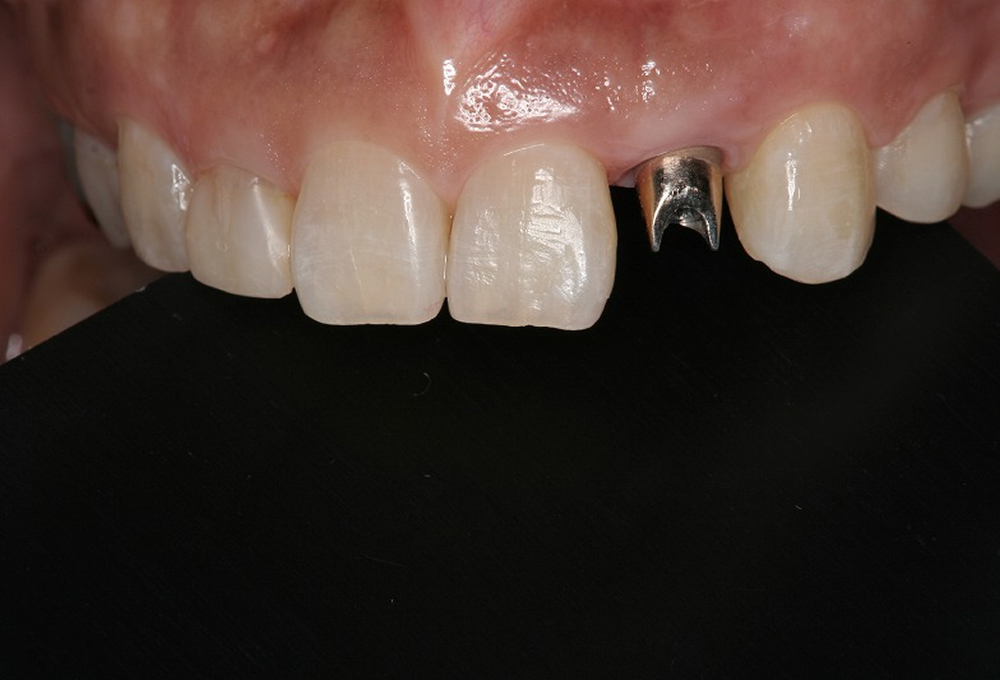

①術前

⑦アバットメント装着後